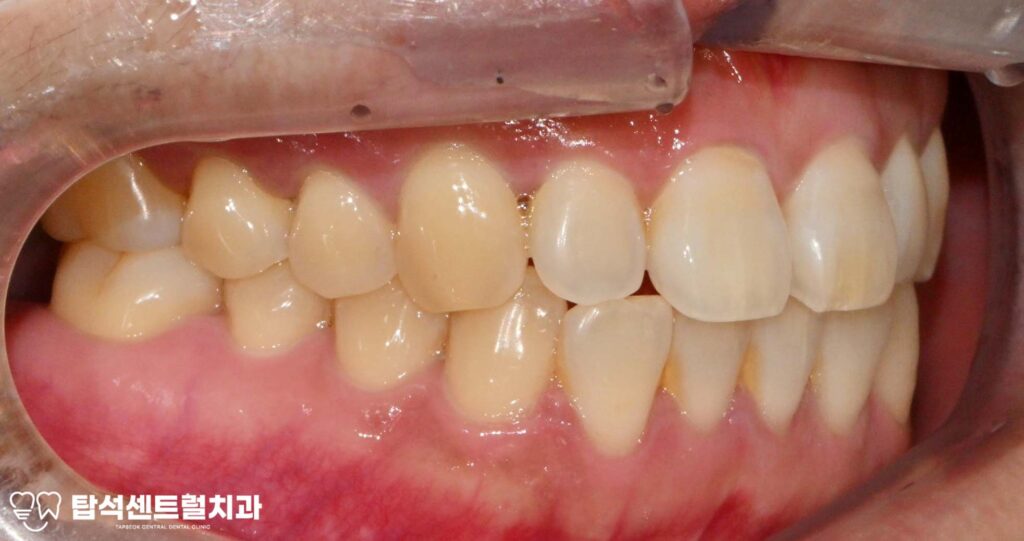

케이스의 경우에는, 아래턱에

임플란트를 식립할 예정입니다.

잇몸뼈의 상태를 확인한 모습입니다.

잇몸 뼈가 남아 있는 양에 따라,

뼈이식의 필요 유무가 정해집니다.